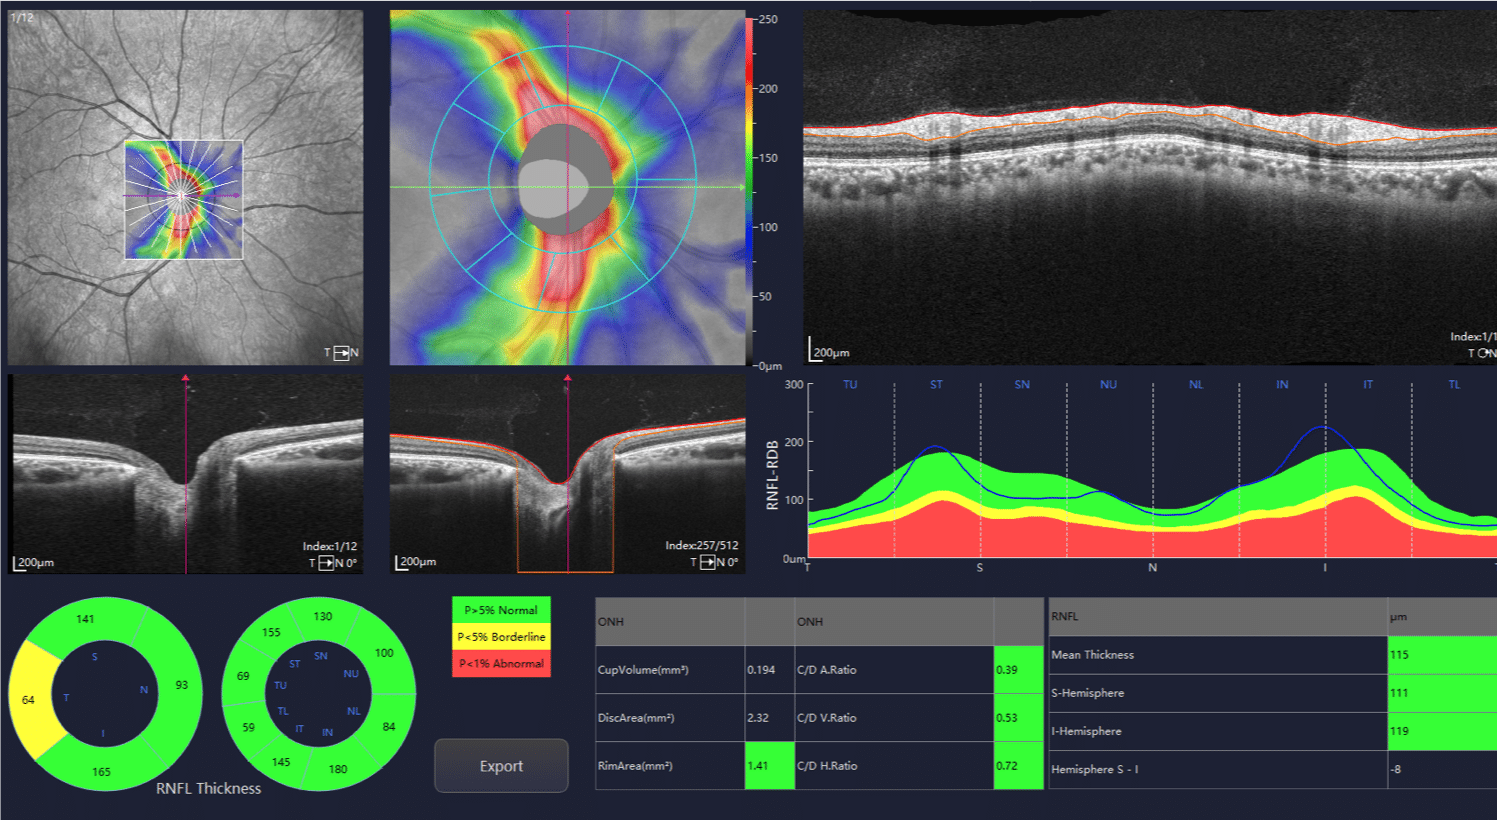

TOWARD PI®Yalkaid 100KHz Full-Range SS-OCT (YG-100Max)

100kHz speed full-range swept-source OCT for anterior and posterior

- Full-Range wide-field Swept Source OCT